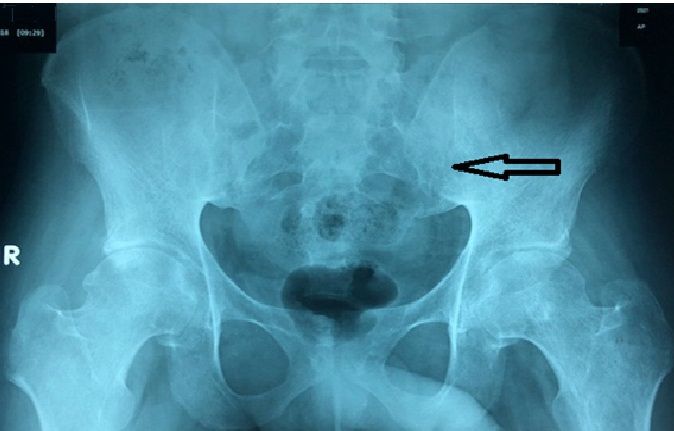

Bệnh viện Sản Nhi Nghệ An, cho biết Khoa Chấn thương chỉnh hình - Bỏng đang chữa trị cho bệnh nhi Đ.N.A. (13 tháng tuổi) trú tại xã Diễn Thịnh, huyện Diễn Châu, Nghệ An, bị hoại tử da do đắp lá thuốc chữa bỏng.

Gần một tháng trước, trong lúc chơi đùa, A. không may bị nước sôi đổ vào người. Phát hiện sự việc, mẹ cháu là chị T.T.U. đã ngâm con trai vào chậu nước để hạ nhiệt.

Khi cởi áo, chị U. phát hiện vùng bụng và ngực con trai bị bong tróc, đỏ tấy. Thay vì đưa cháu A. đến bệnh viện, người nhà khuyên chị đưa con trai đến thầy lang chữa bỏng gần nhà để lấy thuốc.

“Khi đưa con đến khám, vị thầy lang cam kết chữa khỏi vết bỏng của bé trong vòng 15 ngày. Chi phí chữa trị là 25 triệu đồng”, chị U. cho biết.

Tin tưởng và muốn con nhanh khỏi, chị U. đồng ý chữa trị. Bé A. được thầy lang cho thuốc về đắp vào vết bỏng. Ngày thứ 3 điều trị, bé A. xuất hiện tình trạng môi đỏ thâm, sốt cao và tiêu chảy. Chị U. cho con vào Bệnh viện Sản Nhi thăm khám.

Bác sĩ chuyên khoa II Thái Văn Bình, Trưởng khoa Chấn thương chỉnh hình - Bỏng, Bệnh viện Sản Nhi Nghệ An, cho biết bé A. nhập viện trong tình trạng vết bỏng bị sưng nề, chảy dịch đục, vùng cổ, ngực, bụng, cẳng tay phải bị phồng rộp nước, có phần hoại tử đen kèm theo chảy mủ hôi, nhiễm trùng nặng.

Sau gần một tháng điều trị, bé A. đã dần bình phục sau 2 lần ghép da. Theo khuyến cáo của bác sĩ, khi bị bỏng, trước tiên cần cách ly bệnh nhân tránh xa tác nhân gây bỏng, xả vết bỏng dưới vòi nước mát ít nhất 15 phút (tuyệt đối không dùng đá, tránh gây bỏng lạnh).

Việc hạ nhiệt vùng bỏng sẽ giảm sưng, giảm độ sâu của vết thương, giảm nguy cơ gây sốc cho nạn nhân. Nếu có bọng nước, kết vảy, không nên bóc vì dễ gây nhiễm trùng, tổn thương nặng hơn. Tuyệt đối không xoa dầu, bôi kem đánh răng, trứng gà, mỡ trăn, dầu cá, đắp lá chữa bỏng… lên vùng bỏng.